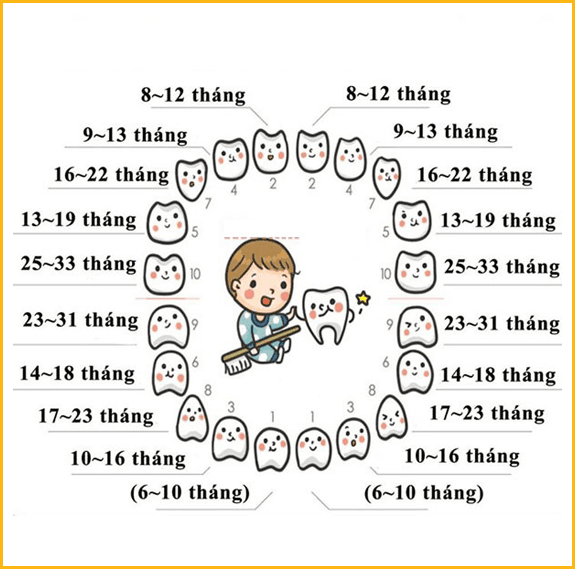

MỌC RĂNG SỮA